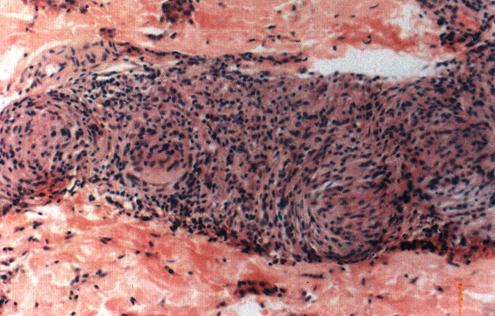

原发性TT(TTp):发病时免疫力很强,临床上病人只有少数或单个典型的TT病损,组织学上为有致密淋巴细胞包绕的上皮样细胞肉芽肿(照片1)。

照片1 结核样型麻风(TTp)

结核样浸润,有大量致密的淋巴细胞围绕在上皮样细胞灶的外周。